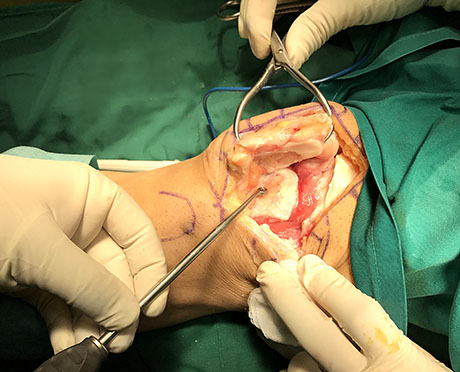

Articular cartilage damage (Outerbridge VI stage), Curetage in the base of the lesion and nanofracture

Severe femoral trochlea arthritis, (Outerbridge VI stage). Curetage and preparing for autologous stem cells implantation